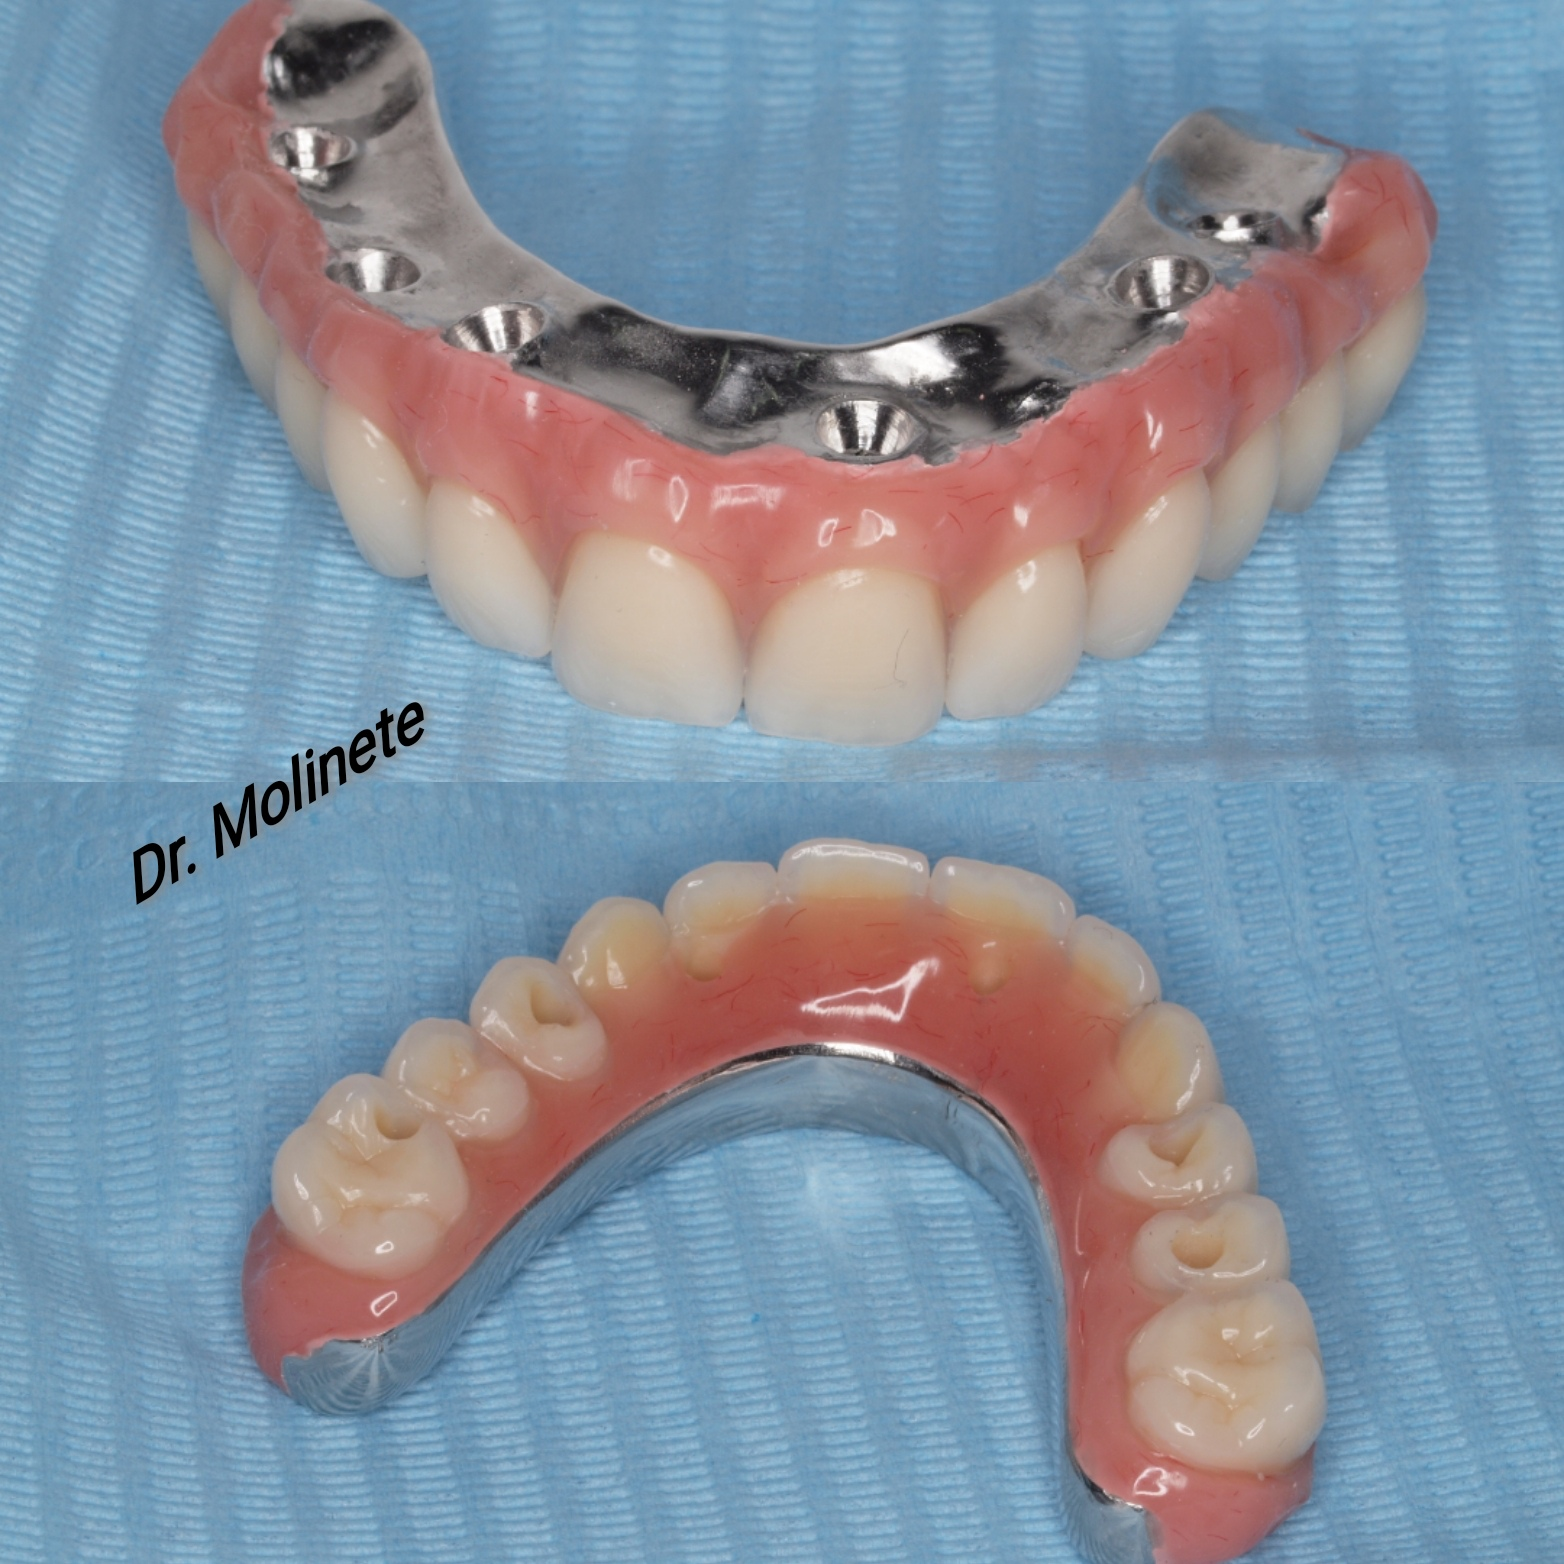

Casos de pacientes

En Clínica Dental Dr. Molinete trabajamos para que los procesos y las intervenciones sean lo más rápido y eficaz posible y con el mejor de los tratos. Tras 12 años de experiencia contamos con diferentes casos de pacientes resueltos de forma óptima.

Aquí te mostramos algunos de ellos.